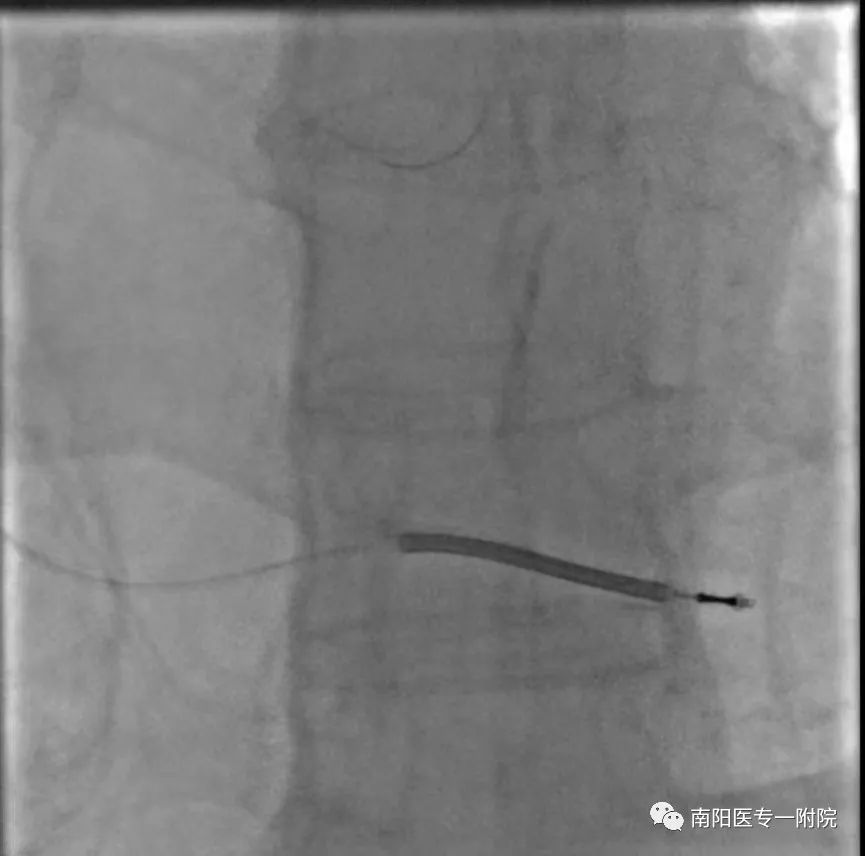

3月17日下午南阳医专一附院心内三团队为86岁高龄反复室速老爷子顺利完成埋藏式心脏除颤装置ICD植入,入院后经冠脉造影明确冠脉情况后,排除冠脉因素,经腋静脉穿刺植入除颤电极,分离胸大肌,除颤装置植入深部肌肉层,采用无创缝合切口!

手术历时1个半小时顺利结束!此次高龄高危病人ICD植入手术的顺利实施再次展现了我院治疗心律失常疾病的实力!(张庆普)